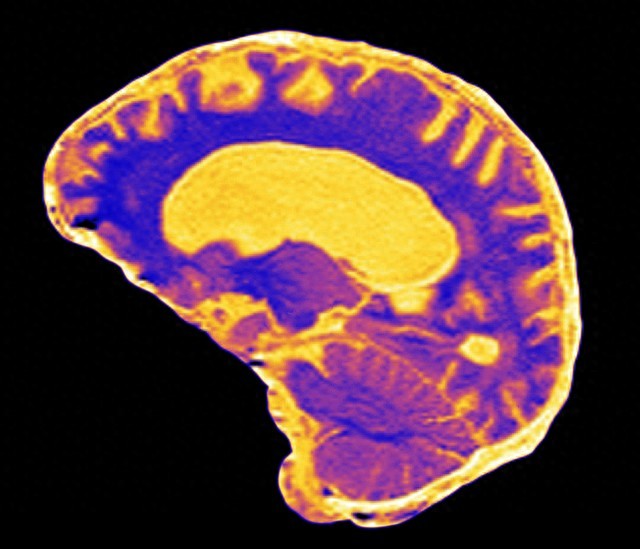

在门诊中我遇到很多语言发育迟缓的孩子,同时也发现很多的家长都存在着一个误区,就是认为孩子长大了自然就好了。我经常跟家长讲,孩子语言迟缓主要问题在髓鞘的信号,它是不通的,神经末梢根本没有连上,如果髓鞘发育不良,那么孩子的语言能力、学习能力也会随之变慢。

3岁男孩总说“火星语”能听懂指令,但表达仅限于“嗯啊”和模糊音节,经神经传导检测发现其语言功能区髓鞘化延迟,信号传导速度仅为同龄人的60%。我们采用低频经颅磁刺激,靶向刺激左侧颞叶,配合口腔肌肉协调训练。2个月后,明明开始模仿叠词;4个月后能主动说“妈妈抱”“喝水”等短语。复查显示髓鞘厚度增加,神经信号传导速度提升至正常范围的85%。

孩子刚开始被诊断为全面发育迟缓,核磁共振显示胼胝体髓鞘发育薄弱。除了语言训练,我们重点进行双侧肢体交替运动(如爬行、抛接球),刺激左右脑连接纤维的髓鞘化。6周后,孩子突然说出完整句子:“爸爸帮我打开”;持续半年干预后,语言能力追平同龄人。妈妈给我们反馈说:“现在每天睡前要讲完所有玩具的名字才肯睡觉。”